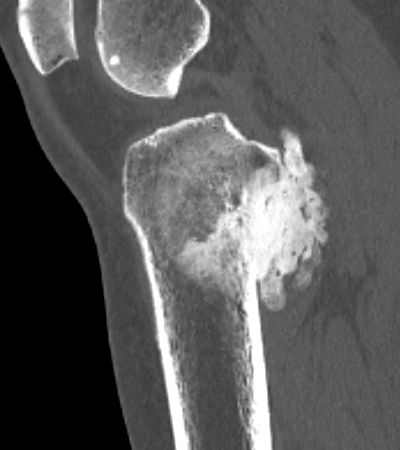

CT

Can be used to differentiate from osteochondroma

1. Parosteal OS

- attached to cortex growing into soft tissue

- normal cortex intact

Parosteal Osteosarcoma proximal tibia